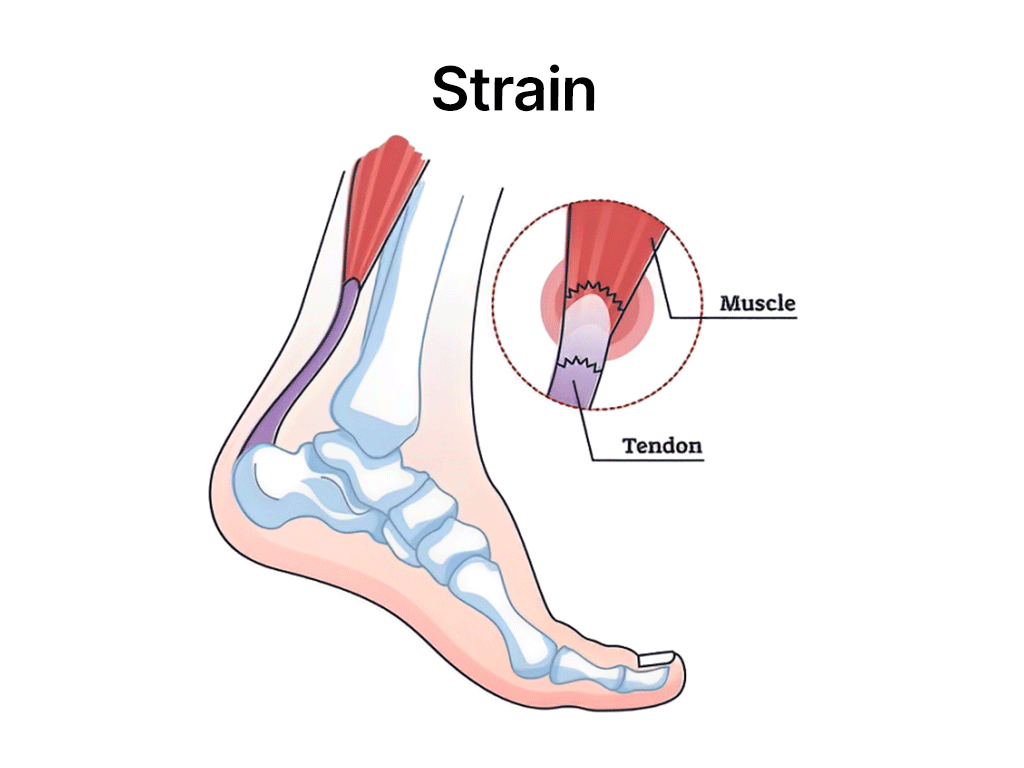

Acute sports injuries occur suddenly during activities. Examples include sprains, strains, fractures, and dislocations. Immediate steps can help manage the injury effectively:

Strains

The most common types include sprains, strains, fractures, dislocations, tendinitis, and concussions.